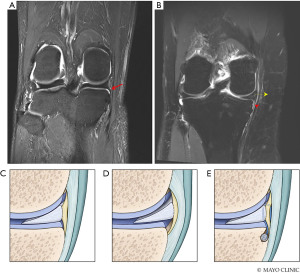

The imaging of choice in identification of MMPRT is magnetic resonance imaging (MRI) (6,8,11,21-24). While the sensitivity for detection of LMPR tears has been reported as relatively low between 33% and 60% (21,23), MRI has been shown to detect MMPRTs with a higher sensitivity of 86–90% and specificity of 94–95% (25). This decreased sensitivity for LMPR tears on MRI can be attributed to the orientation of the posterior horn of the lateral meniscus as it continues to the posterior root, which is often more parallel to the plane of the sagittal MRI when compared to the orientation of the posterior horn and root of the MM. The meniscal root is best visualized on the T2-weighted sequences with several key direct signs that indicate MMPRTs (26). On T2-weighted sagittal imaging, there may be an absence of normal meniscal signal at the level of the MMPR, known as the “ghost” sign (Figure 3A). On axial imaging, there may be a linear hyperintensity perpendicular to the meniscus representing a radial tear (Figure 3B); on coronal imaging, there may be a vertical linear defect at or adjacent to the MMPR known as the “cleft” sign (Figure 3C) (26,27). A more recent “giraffe” sign has also been described, which represents a broad trapezoidal-shaped MM body on coronal T2 sequences (Figure 4). The giraffe sign was present in 81.7% of MMPRTs (28). Furumatsu et al. demonstrated that 91.7% of patients with MMPRTs have at least two of the aforementioned signs (radial tear on axial sequence, cleft, ghost, and giraffe neck signs) present on MRI, whereas only 5% of patients with other MM tears have at least two of these signs present on MRI (28).

Other indirect findings on MRI in the setting of MMPRTs include meniscal extrusion (defined as >3 mm of meniscus medial border to the medial tibial plateau typically best appreciated on a coronal MRI sequence just posterior to the MCL, shown in Figure 4) (26,29-31), medial tibial plateau subchondral edema (8,19,24,26), and subchondral edema present at the posterior tibial plateau that is typically meniscus-covered (32) or at the site of the MMPR bony insertion (33). A potential early finding that may precede a degenerative MMPRT is the “spreading roots” sign characterized by edema appearing to spread out from the subchondral bone at the MMPR bony insertion (34).